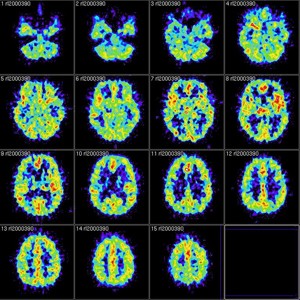

Brain scan by  Reigh LeBlanc on Flickr